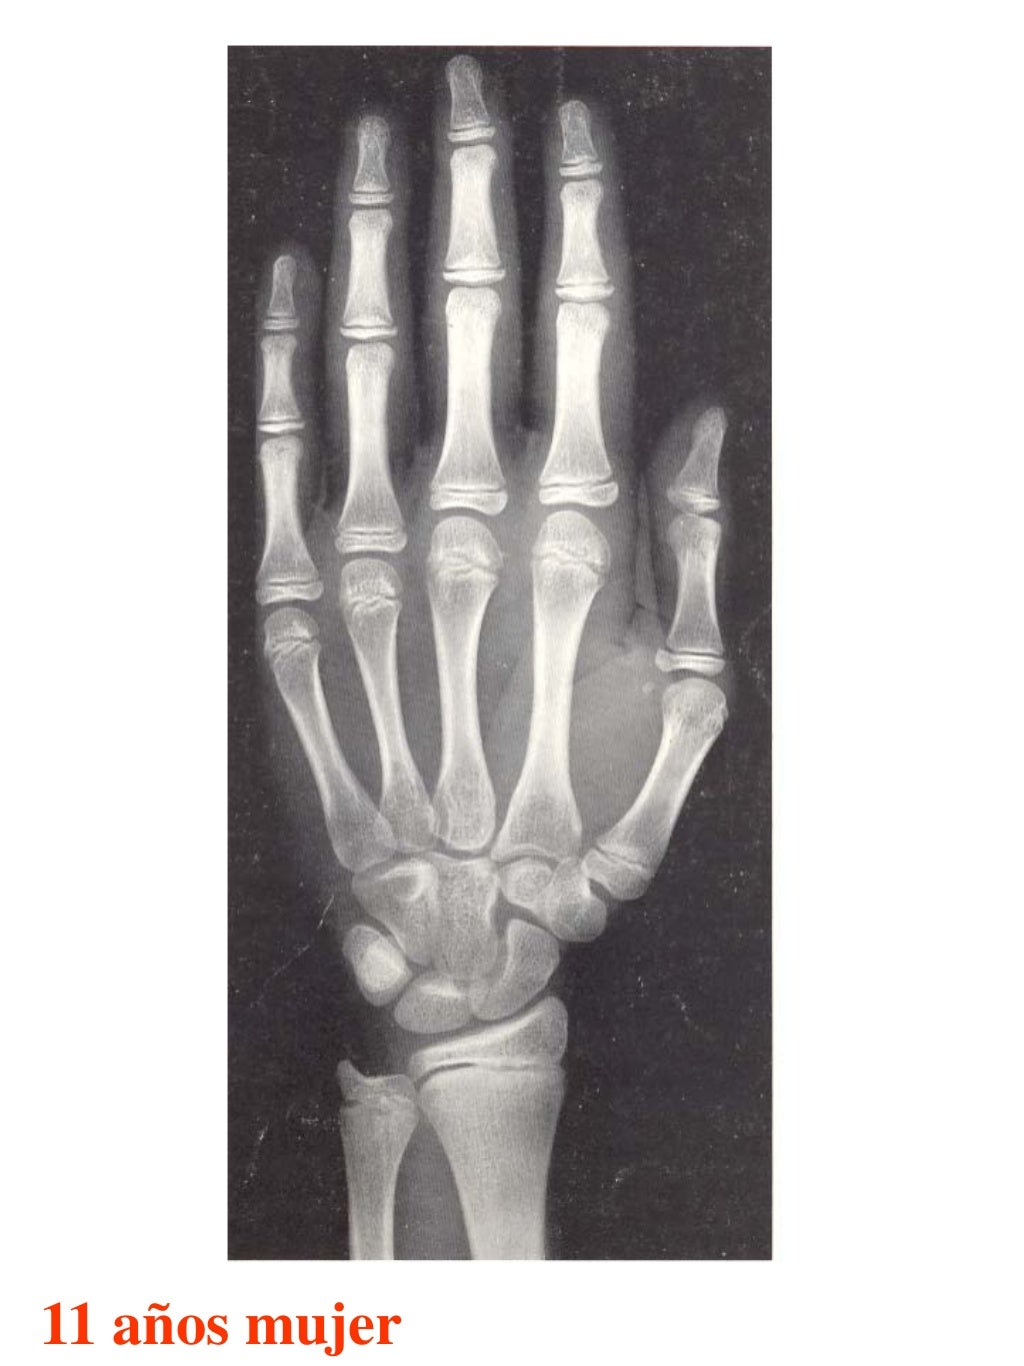

Tablas De Greulich Y Pyle . Scribd is the world's largest social reading and publishing site. This systematic review summarizes the. The radiographic atlas of skeletal development of the hand and wrist by ww greulich and si pyle is a classic radiological. The standards established by greulich and pyle, undoubtedly the most popular method, consist of two series of standard plates. The greulich and pyle method is one of the two main ways to assess the bone age of children. El documento lista las edades. Both main methods of bone age. 153 recomendaciones • 616,869 vistas. Atlas greulich y pyle | pdf | descarga gratuita. The greulich and pyle atlas is used to estimate the age of children and adolescents.

Tablas De Greulich Y Pyle The standards established by greulich and pyle, undoubtedly the most popular method, consist of two series of standard plates. The standards established by greulich and pyle, undoubtedly the most popular method, consist of two series of standard plates. El documento lista las edades. This systematic review summarizes the. The greulich and pyle method is one of the two main ways to assess the bone age of children. Both main methods of bone age. Scribd is the world's largest social reading and publishing site. 153 recomendaciones • 616,869 vistas. Atlas greulich y pyle | pdf | descarga gratuita. The greulich and pyle atlas is used to estimate the age of children and adolescents. The radiographic atlas of skeletal development of the hand and wrist by ww greulich and si pyle is a classic radiological.